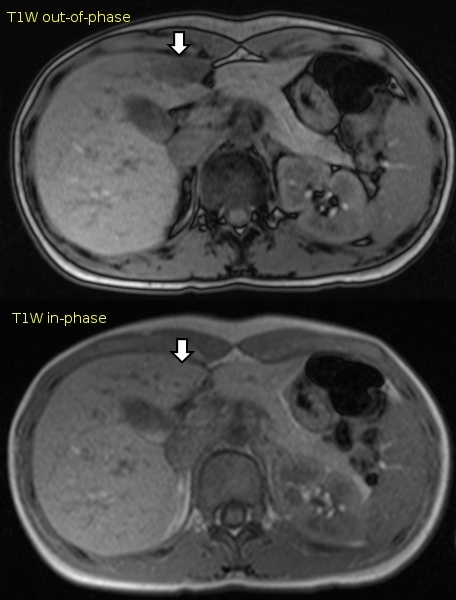

Q

Abdome: doença hepática difusa

V ou F?

As lesões focais hepáticas na imagem são suspeitas para metástases.

Sequências GRE em fase/fora de fase.

A

Falso.

As lesões na imagem correspondem a esteatose multifocal/multinodular.

Aspecto típico da esteatose focal nos diversos métodos?

1. Sinal intermediário em T2;

2. Queda de sinal em T1 fora de fase;

3. Sem realce significativo;

4. Hiperecogênico no USG;

5. Hipoatenuante na TC;

6. Predileção por segmento IV / perivesicular;

7. Não distorce vascularização

Sem efeito de massa

Sequências gradiente-eco ponderadas em T1 em fase e fora de fase demonstram infiltração gordurosa focal à direita da fissura do ligamento redondo. Há perda de sinal nas imagens fora de fase. A perda de sinal ocorre quando moléculas de água e gordura ocupam o mesmo voxel, com interferência negativa entre seus sinais. Isso decorre das diferentes velocidades de precessão de gordura e água no mesmo campo magnético.